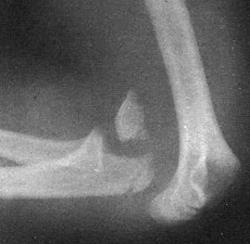

Задний вывих

Возникает в результате непрямой травмы (падения на переразогнутую в локтевом суставе вытянутую руку). Капсула локтевого сустава при этом разрывается, нижняя часть плеча смещается вперед. Задний вывих предплечья может сочетаться с переломом мыщелков плечевой кости у взрослых или с переломом надмыщелков плеча у детей.

Пациент с задним вывихом предплечья жалуется на резкую боль в области повреждения. Рука находится в вынужденном положении легкого сгибания. Сустав деформирован, увеличен в объеме, активные движения в локтевом суставе невозможны, при попытке пассивных движений определяется характерное пружинящее сопротивление. При осмотре спереди предплечье выглядит укороченным. Локтевой отросток смещен кверху и кзади. В области локтевого сгиба пальпируется нижняя часть плечевой кости.